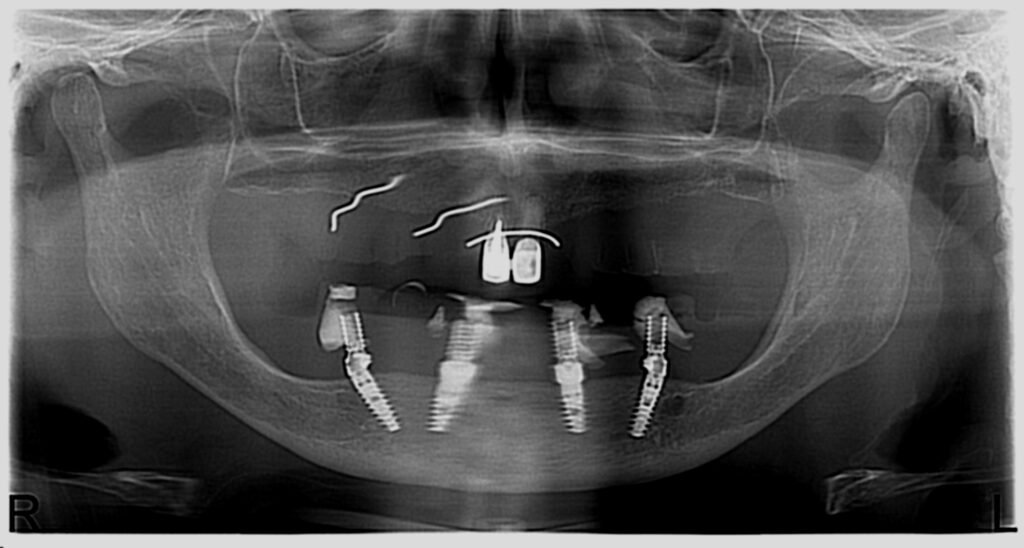

Réhabilitation complète avec mise en charge immédiate (4 implants bas / 6 implants haut)

Le patient se présente avec des dents qui bougent, en haut et en bas.

Nous avons commencé par la mâchoire inférieure avec 4 implants et une mise en charge immédiate.

Trois mois après, le haut a été fait avec le même principe avec 6 implants.

Cette fois-ci, il existait un déficit osseux, résolu par une technique d’expansion sans avoir recours à la greffe d’os.

Les prothèses réalisées sont vissées, ce qui permet de les enlever, les nettoyer une fois par an, ou résoudre n’importe quel problème.

Images :